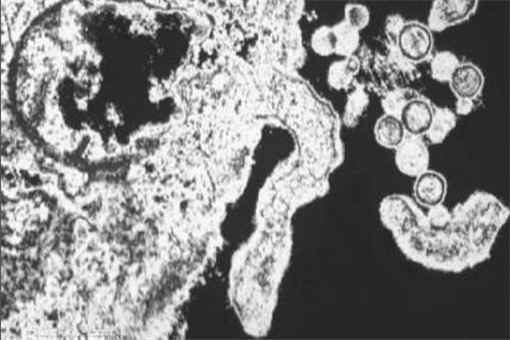

公开资料显示,汉坦病毒出血热为人畜共通传染病,传播宿主为啮齿类动物,尤其是老鼠,人一旦吸入或接触遭鼠粪尿污染带有病毒飞扬的尘土、物体或被带病毒啮齿类动物咬伤,即可能受感染,其潜伏期数天至两个月,一般会出现发烧、头痛、倦怠、腹痛、下背痛、恶心、呕吐、不等程度出血现象并侵犯肾脏。